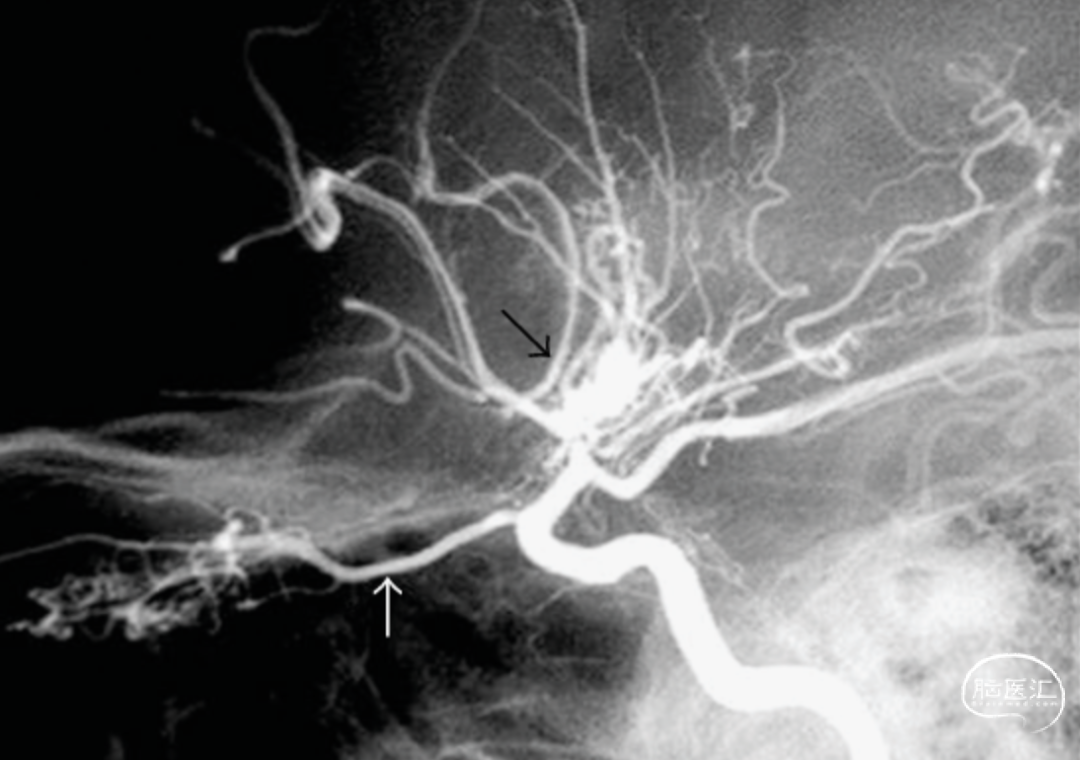

直接的颅内外动脉搭桥嘛,就是直接把颈外动脉的分支和缺血的脑半球里的皮质动脉连起来。间接的血运重建呢,就是拿颈外动脉分支供血的那些组织,转移到缺血的脑半球表面,让它和下面的皮质血管搞个侧支循环,好让缺血区恢复供血。